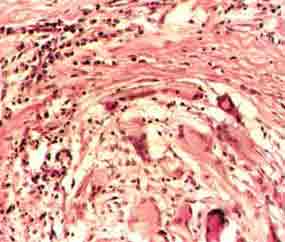

1.典型異物反應為巨噬細胞及異物巨細胞包圍異物,細胞質內可見有吞噬的異物,尚可見異物如縫線、液狀石蠟油、矽鹽毛髮等均可引起異物反應。

2.異物過敏反應,可出現上皮樣細胞構成的結核樣結節,具有巨細胞及乾酪樣壞死,但缺乏或少有吞噬異物現象鈷鈹或紋身顏料可引起異物過敏反應。

3.一些特異性異物肉芽腫,如紋身肉芽腫可見顏料顆粒矽肉芽腫為非結核性肉芽腫為多數巨噬細胞和多核細胞的炎症浸潤,可見折光性強的針狀矽結晶。